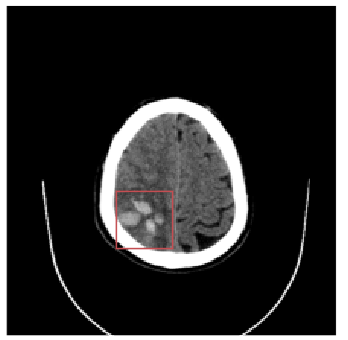

Inverse Problems in Radiology